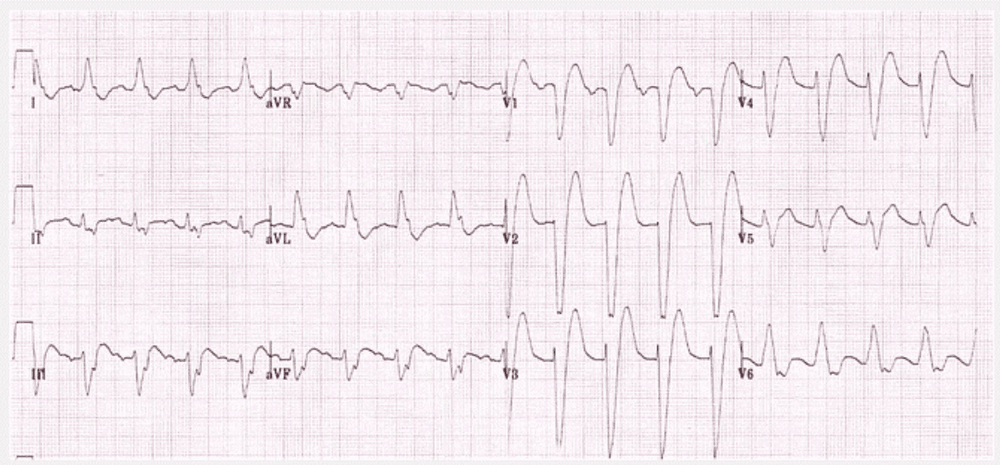

3. Phân tích các điện tâm đồ cơ bản

Cách xem kết quả điện tâm đồ cơ bản như sau:

3.3. Đặc điểm phức bộ QRS

- Rộng không quá 12 ms (3 ô nhỏ)

- Thời gian <0,10 s.

- Sokolow = (SV1 + RV5) < 35mm.

- R/S < 1 ở V1, V2; R/S > 1 ở V5,V6.

- Ở chuyển đạo trước tim phải (V1): S >> R

- Ở chuyển đạo trước tim trái (V5,6): cao không quá 25 mm

- Ở chuyển đạo trái có thể có sóng Q do khử cực vách liên thất nhưng: sâu không quá 2mm và rộng không quá 1mm.

3.4. Bất thường QRS

- Rộng quá: block phân nhánh; nhánh, nhịp ngoại tâm thu...

- Cao quá: phì đại thất

- Dày thất phải: trục phải (>110 độ); R >>S ở V1, V2; S sâu ở V5-6

- Dày thất trái: trục trái (< 0 độ); R cao ở V5,6 (>= 25mm); S sâu ở V1-2; chỉ số Sokolow-Lyon (SV1 + RV5 hoặc RV6) >= 35mm.